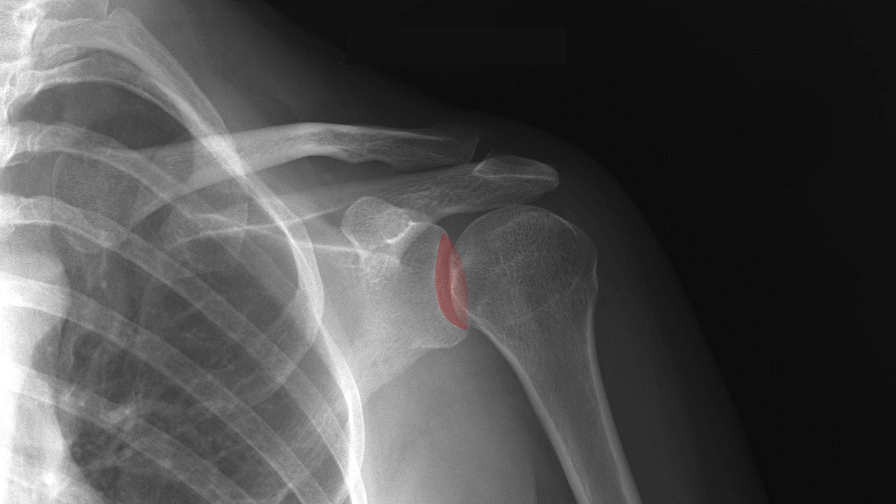

Lateral view of the right knee lateral view of the right knee. The patellar ligament is the anterior ligament of the knee joint. Arthritis occurs when there are inflammation and damage to the cartilage of the knee joint.arthritis can lead to swelling, pain, and difficulties with activities.